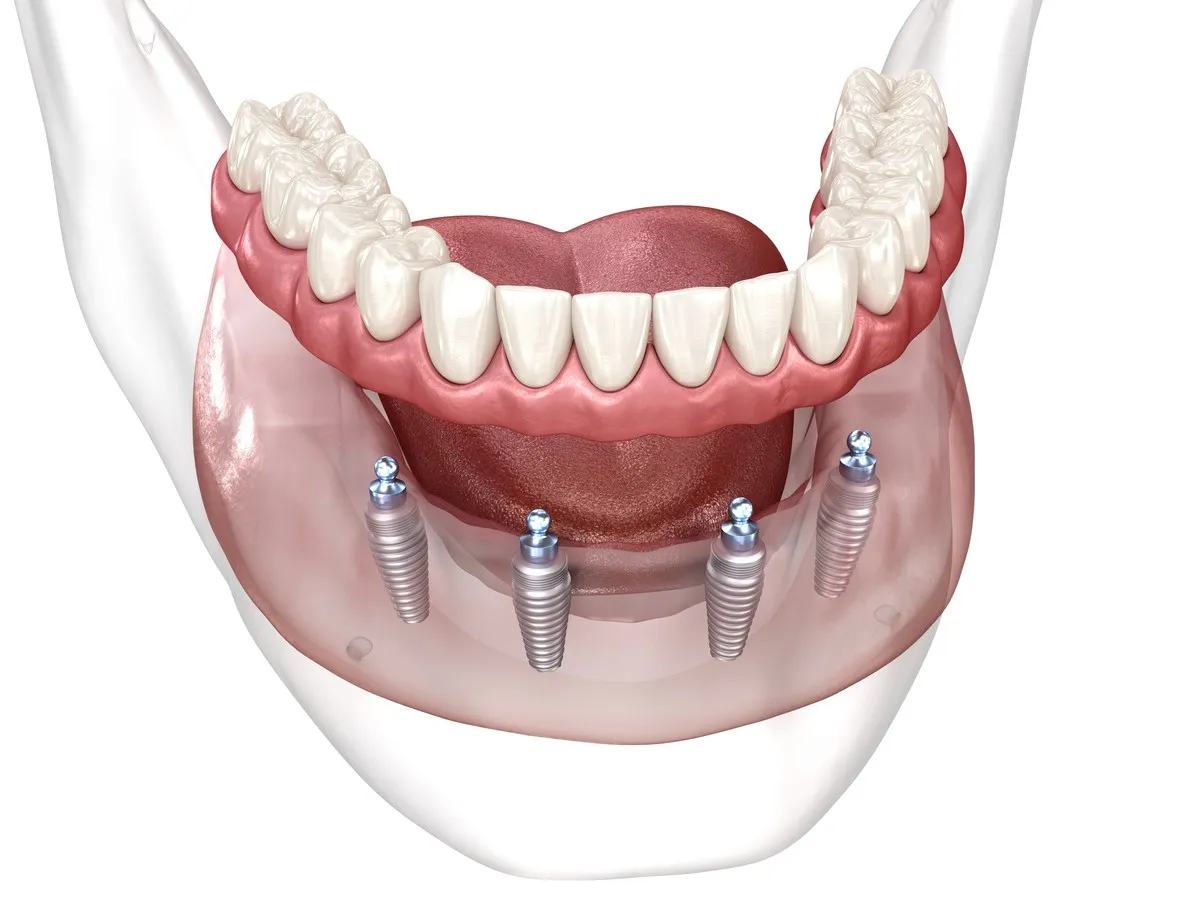

Implants, All-on-4 & All-on-6 — Done Right

Straumann, Neodent & Dentium implants placed by internationally trained specialists — at 60–80% less than Australian, UK and US prices. Written fixed quote before you fly.

The price difference isn't from cutting corners — it's structural. Vietnam's cost of living, dental labour, and clinic overheads are a fraction of Australia's. We use the exact same Nobel Biocare, Straumann, and Neodent implants your Australian specialist would use — purchased from the same global supply chain. The difference is what surrounds the implant, not the implant itself. We'll send you the published implant specs and pricing so you can verify this directly.

Single Implant, All-on-4 or All-on-6?

The right treatment depends on how many teeth you've lost, your bone density, and your goals. Here's how the three options compare — so you arrive with a clear picture.

Not sure which option is right for you? Send us a photo of your smile or a brief description of what you'd like fixed. Our implantologist — not a salesperson — will review your case and tell you exactly which treatment is clinically appropriate, with a fixed quote in your currency. Complex cases — bone loss, failed implants, full extractions — are welcome.

An Implant That Costs $4,500 at Home Costs $835 Here

All-on-4 full arch starts at $4,214 — versus $20,000–$28,000 in Australia, the UK or the US. The materials are identical. The brands are the same. The difference is the cost of doing business in Vietnam, not a compromise in quality.